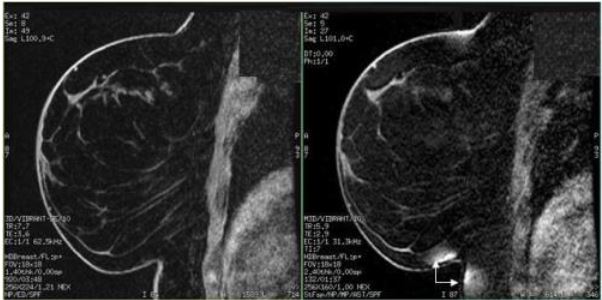

BrightDynamic (with and without contrast) or multiphase with Fat SAT or Flex

• Use VIBRANT with fat SAT(special), VIBRANT Flex, or VIBRANT DISCO

• Place the center frequency on water for fat SAT

Figure 6. No slicone in breast: Left = VIBRANT with Flex, right = VIBRANT